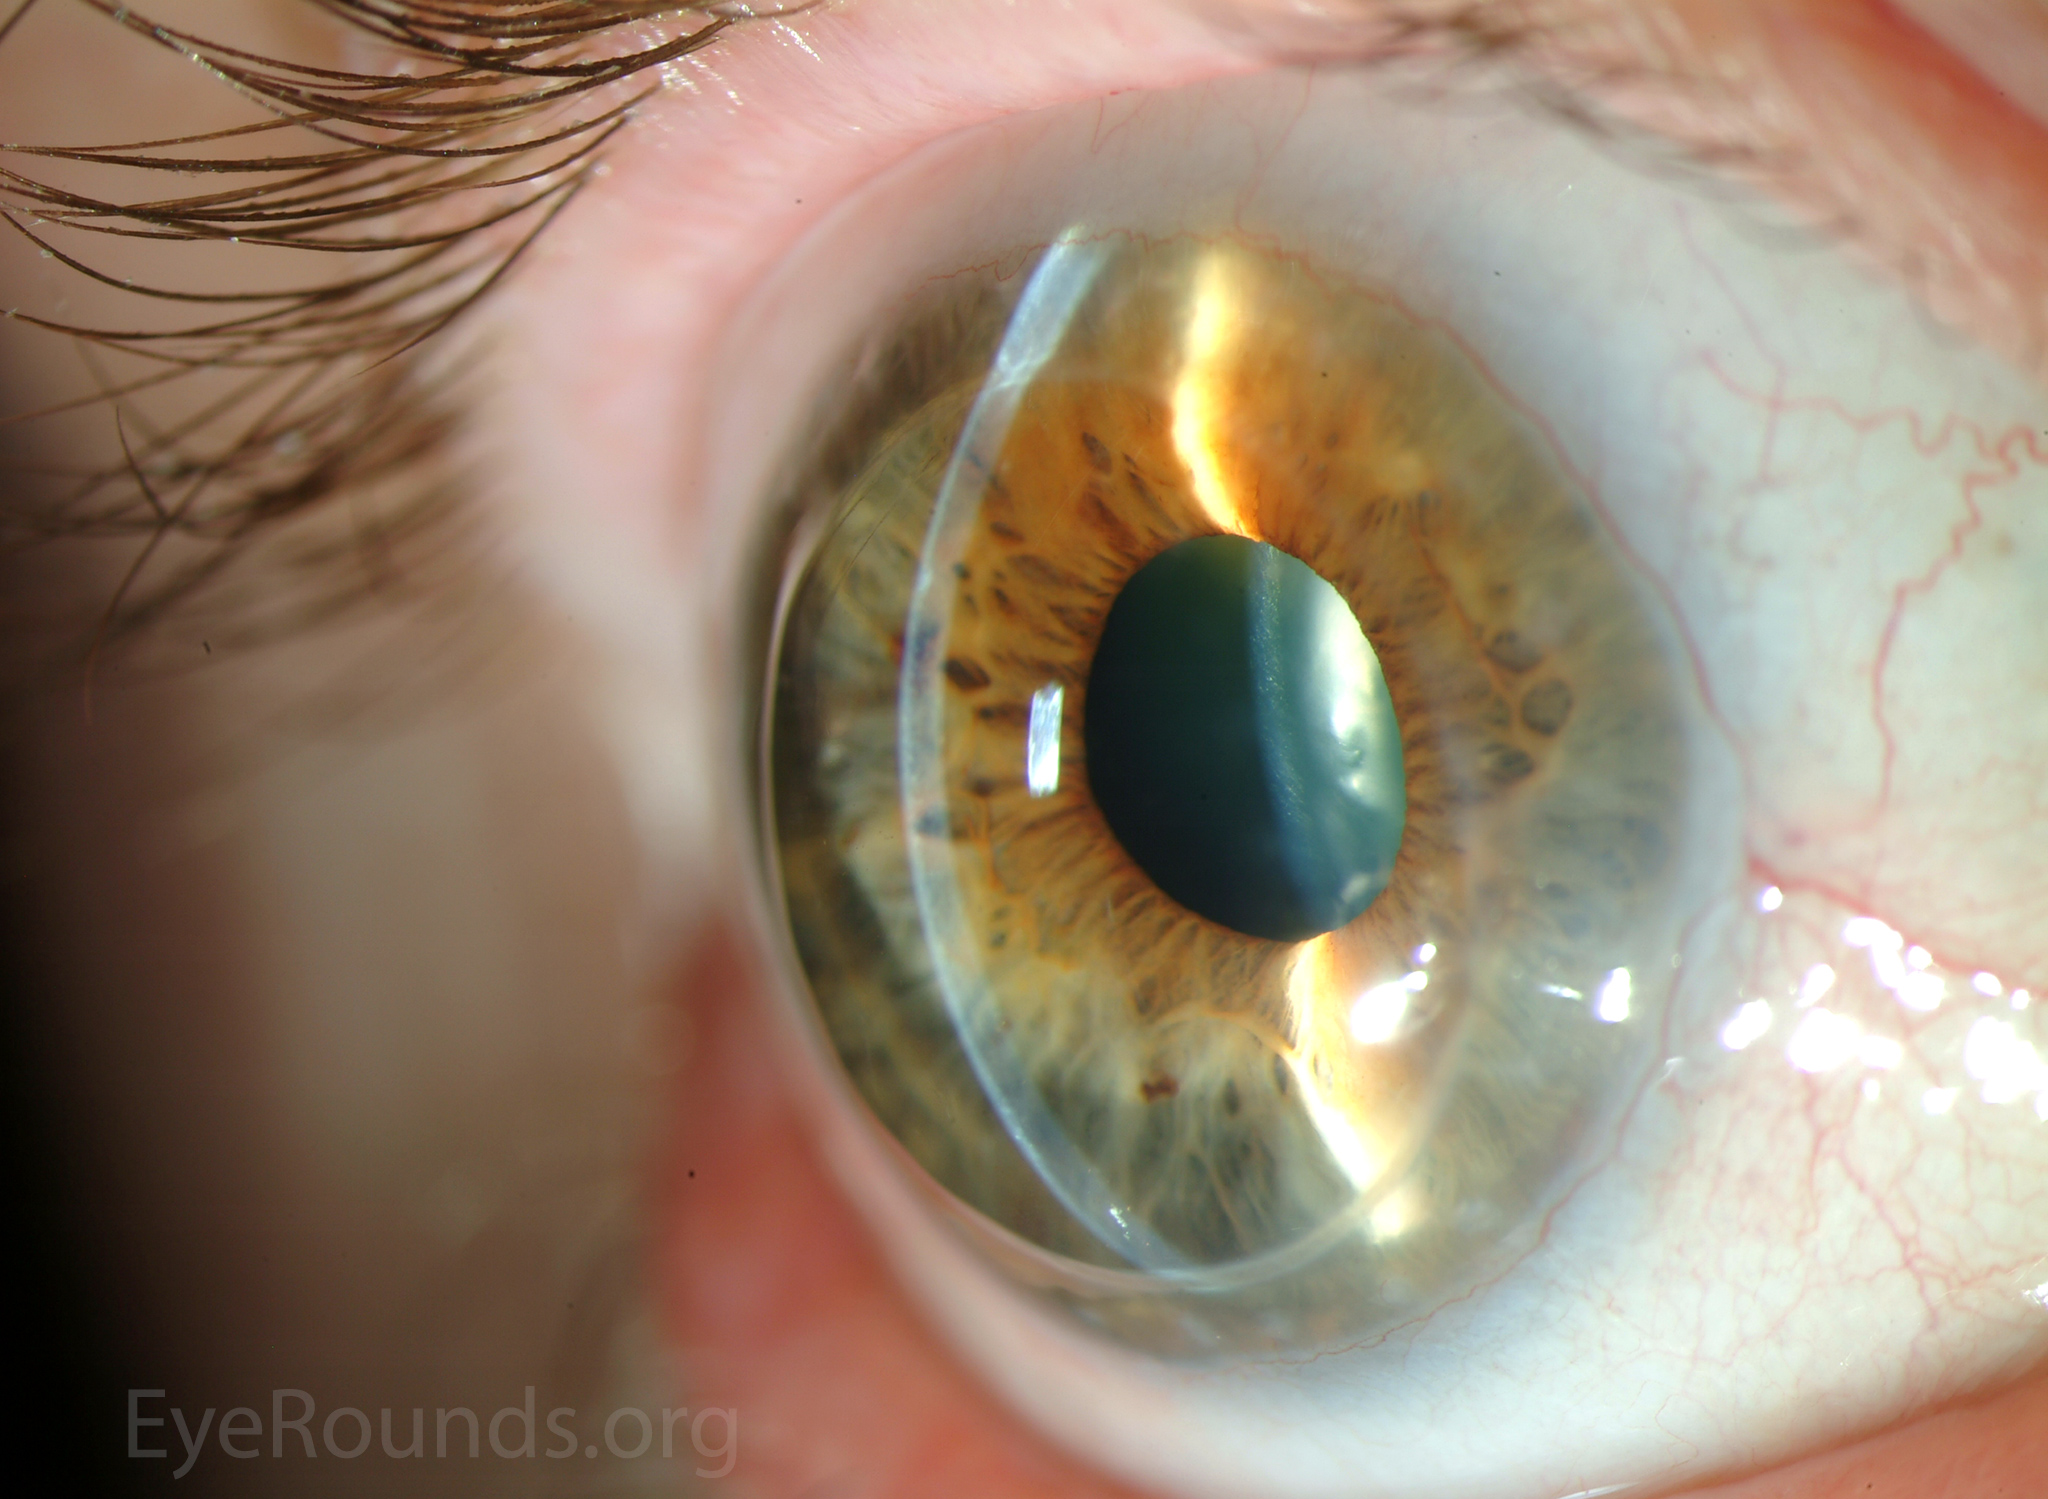

PK is a full-thickness transplant procedure, in which a trephine of an appropriate diameter is used to make a full-thickness resection of the patient's cornea, followed by placement of a full-thickness donor corneal graft. Interrupted and/or running sutures are placed in radial fashion at equal tension to minimize post-operative astigmatism (Figure 2). Later, the sutures are removed selectively to reduce the amount of astigmatism present. A transplant can last decades with proper care (Figure 3). While once the most prominent type of corneal transplant, PK has been supplanted by partial thickness techniques for endothelial dysfunction without significant stromal scarring. PKs are performed primarily for visually significant stromal scarring, opacities with an uncertain status of the endothelium or significant posterior corneal involvement, corneal ectasia (such as keratoconus and pellucid marginal degeneration, especially if there is history of hydrops), combined stromal and epithelial disease (such as Peters anomaly), and infectious or non-infectious corneal ulcerations or perforations (1, 14). A variant of the procedure, the mini-PK, can be used to treat more focal defects in the cornea (Figure 4).